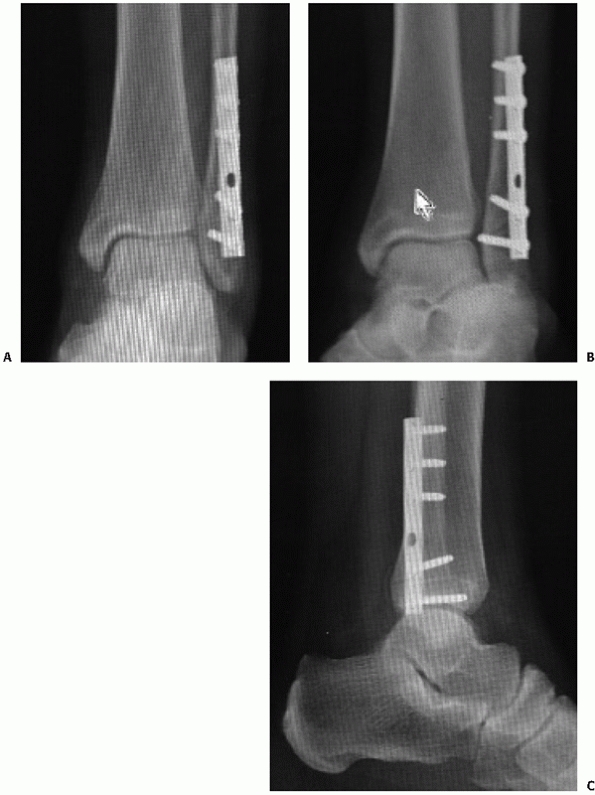

![]() |

FIGURE 57-2 Example of standard ankle trauma series including AP (A), mortise (B), and lateral (C).

anteroposterior (AP), 15-degree internal rotation AP (mortise), and

lateral views (Fig. 57-2). Using these three

views is best for ensuring that the diagnosis of fracture instability

is made; however, AP and lateral views only can be sufficient and may

provide a great deal of information regarding the integrity of the

ankle.26 To manage the large volume